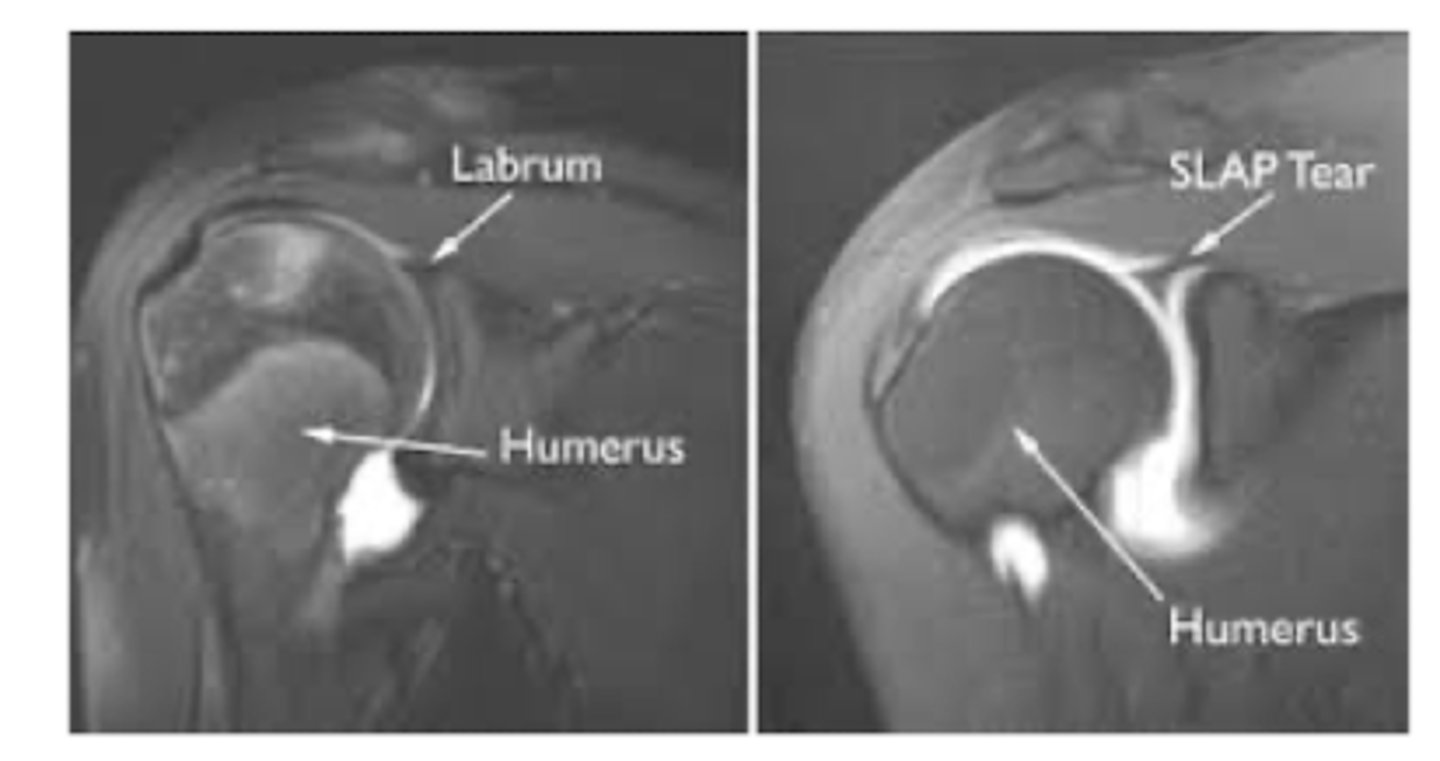

What is a SLAP injury?

superior labrum anterior-to-posterior lesions/tears

T/F. SLAP is often a diagnosis of exclusion.

TRUE - can be confirmed at the time of surgery

What THREE special tests can evaluate for shoulder labral tears?

O'brien

Clunk

Anterior slide

What is the GOLD STANDARD for diagnosing SLAP?

MRA (arthrogram)

What is the treatment for SLAP?

NSAIDs

PT

Surgery